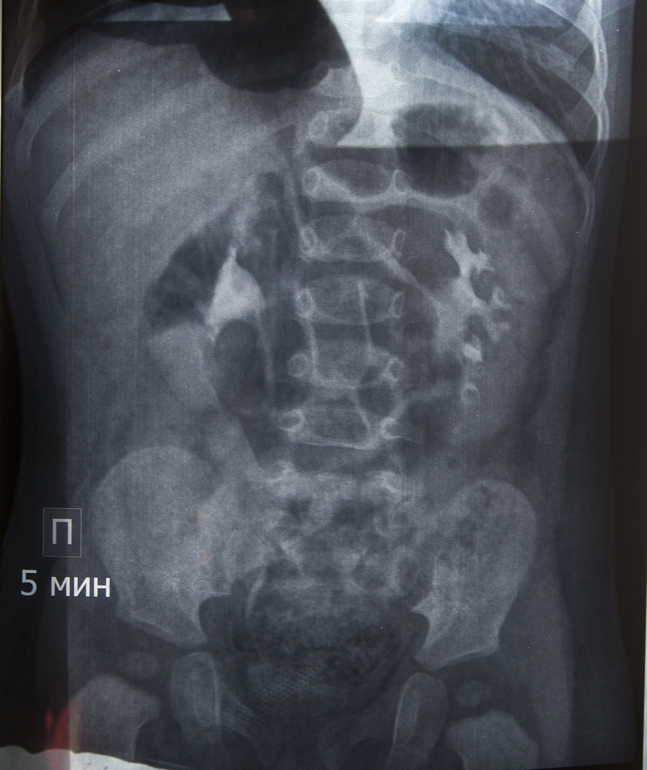

Ситуация 1: ребенку 1 год и 3 мес, в год прошли обследование (в/в уро- и цистография с контрастом), был поставлен диагноз "левосторонний гидронефроз 1 ст, фимоз". На апрель назначена операция по удалению крайней плоти. Нефролог говорит, что пока основной причиной гидронефроза признается именно фимоз. Дополнительных исследований (например, доплерография сосудов почек) не назначалось. Мой вопрос заключается в том, как часто (если таковое вообще возможно) фимоз может стать исключительной причиной гидронефроза? Если дело только в нем, операция окажется оправданной, если же препятствие в другом месте, ребенку предстоят "лишние" испытания, ведь вероятность того, что физиологический фимоз пройдет сам, высока. Для полноты картины я могу предоставить оцифровку рентгеновских снимков и выписку из истории болезни.

Если возможно, не могли бы Вы оценить результаты рентгенографического обследования моего младшего сына? На сколько качественно, на Ваш взгляд, были сделаны снимки? Согласно заключению нефролога, рефлюкс исключен. Если есть стриктура мочеточника (любой этиологии), должна ли она визуализироваться на рентгеновском снимке, или бывают случаи, которые проще диагностировать на УЗИ с диуретиком?

Я не берусь судить заочно, думаю слева нужно посмотреть на предмет абберантного сосуда в проекции пиело-уретрального сегмента